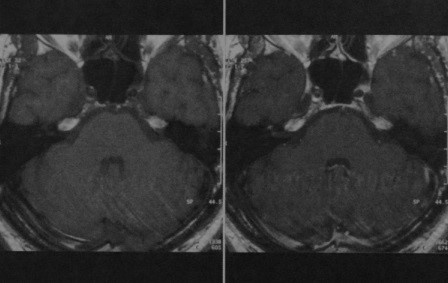

МРТ внутренних слуховых проходов в аксиальной проекции:

(а) Т1 до введения контраста.

(б) Т1 после введения гадолиния (обратите внимание на усиление сигнала от сигмовидного синуса и слизистой околоносовых пазух).

(в) Т2 (ликвор и глазные яблоки выглядят яркими),

а, мозжечок; b, сосцевидный отросток; с, четвертый желудочек; d, сонная артерия; е, сигмовидный синус;

f, улитка; д, сонная артерия; h, височная доля; i, мостомозжечковый угол (обратите внимание на слуховой и нижний вестибулярный нервы, которые входят во внутренний слуховой проход).